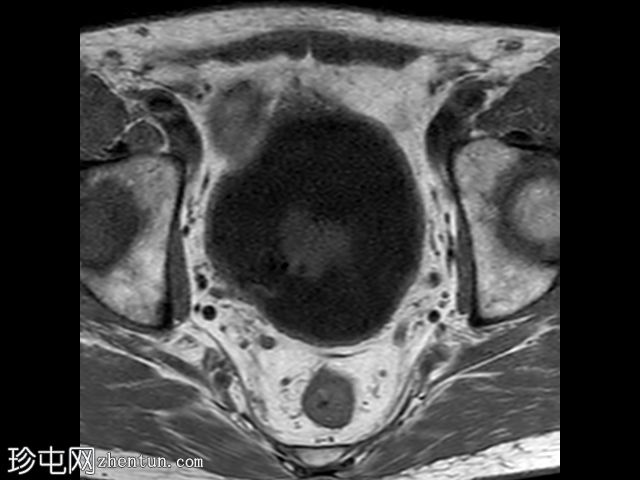

轴位

T1加权像

在T1和T2加权像上,于膀胱底部及右下外侧面偶然发现一处呈蛇形缠绕状的低信号区。动态序列中可见快速对比增强,提示所有影像学表现均源于血管,信号缺失与动静脉畸形有关,该畸形至少由膀胱下动脉供血,并由同侧局部扩张的静脉回流。